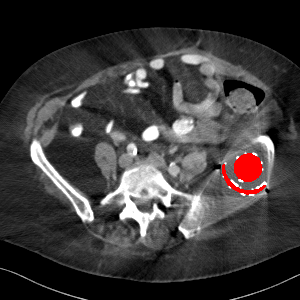

Visual comparison. As shown in Fig. 5, metallic implants such as spinal rods and hip prosthesis cause severe streaky artifacts and metal shadows, which obscure bone structures around them. cGan-CT cannot recover image intensity correctly for both cases. Sinogram domain or dual-domain methods perform much better than cGan-CT. LI, NMAR, and CNNMAR introduce strong secondary artifacts and distort the whole images. In NMAR images, there are fake bone structures around the metals, which is related to segmentation error in the prior image from strong metal artifacts. The segmentation error is also visible in NMAR sinogram. CNNMAR cannot restore the correct bone structures between rods in case 1. The tissues around the metals are over-smoothed in DuDoNet because LI sinogram and image are used as inputs, and the missing information cannot be inferred later. Our model retains more structural information than DuDoNet and generates anatomically more faithful artifact-reduced images.

Visual comparison. Fig. 7 shows two clinical CT images with metal artifacts. Case 1 is with moderate metal artifacts. cGan-CT does not suppress the artifacts completely and generates some fake details. LI, NMAR, CNN-MAR remove all the artifacts but introduce new streak artifacts, which is caused by the discontinuity in the corrected sinogram. DuDoNet outputs over-smoothed sinogram, which leads to blurred tissues close to the metal implants, such as muscle and bone. Only our model can provide realistic enhanced sinogram and remove the artifacts while retaining the structure of nearby tissues. Case 2 is very challenging as the rods bring strong metal shadows and bright artifacts around the vertebra. cGan-CT recovers the shape of vertebra but changes the overall image intensity. Other sinogram inpainting methods fail as the soft tissue and bone near the rods are heavily distorted. Our model removes part of the dark bands and reproduces correct anatomical structures around the rods.